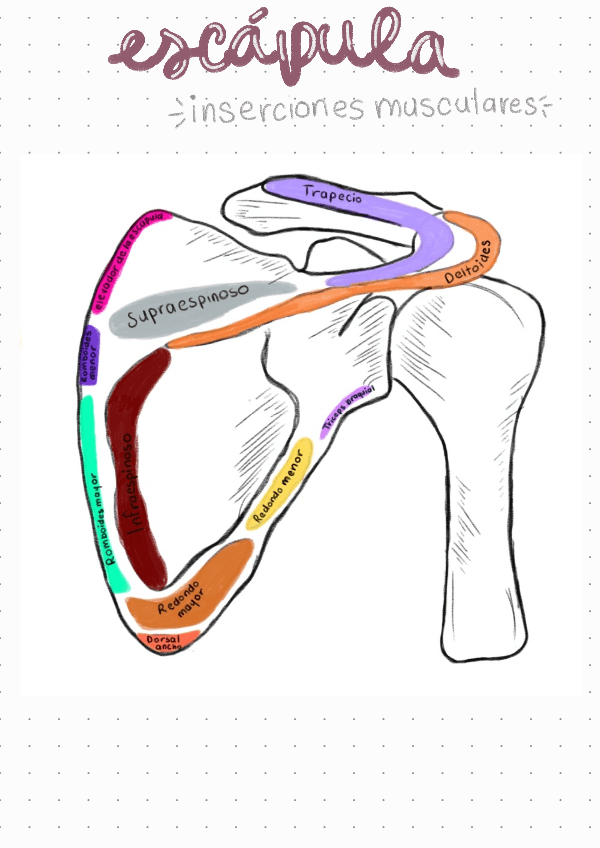

He publicado nuevos apuntes de 1º Estructura y Función Humana: ANATOMIA-ESCAPULA.pdf

3 páginas